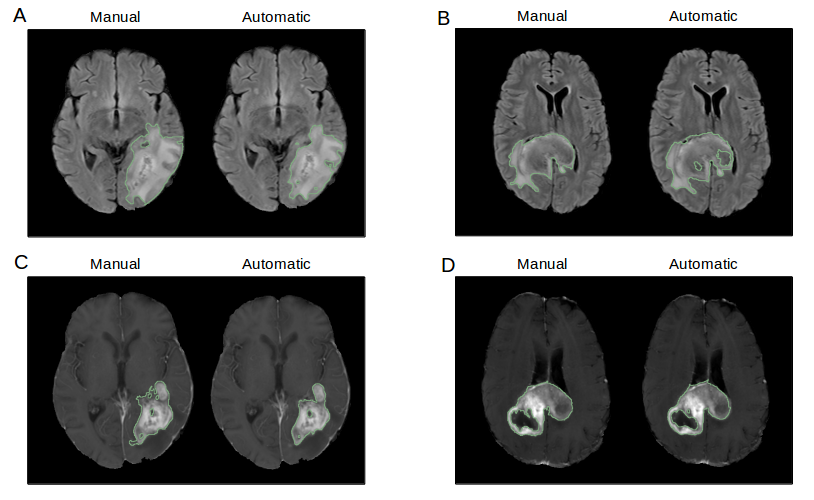

5.2 Glioblastoma Segmentation

Pathological volume monitoring, and thus pathological tissue segmentation, is essential for assessment of treatment response and prognosis in glioblastoma treatment. [40, 41] Furthermore, volumes and imaging features derived from delineated tumor regions can be used for downstream prediction of molecular biomarkers, treatment response, progression, and survival.[42, 43, 44, 45]. Unfortunately, manual delineation of tumor boundaries can be challenging and subject to inter- and intra-rater variability, resulting in low reproducibility even among expert radiologists and oncologists. Additionally, it is a laborious task especially for high-resolution scans which can have numerous image slices. This diverts clinicians’ time away from other clinical and research tasks, as well as other patients. There are two tumor regions that are of key interest to the clinician. The first is the whole tumor, which consists of edematous tissue, non-enhancing, enhancing tumor, and necrosis. This is best seen on the T2 FLAIR sequence and represents the total tumor burden. The second is contrast-enhancing tumor, which represents regions of breakdown of the blood brain barrier. [46]

The Glioblastoma Segmentation module uses two 3D U-Net architectures. The first creates a binary labelmap of a region-of-interest defined as whole tumor. The output of this network is fed as an additional channel into a second network, which predicts a binary labelmap of enhancing tumor alone (Figure 6). Both networks take in 32x32x32mm patches extracted from FLAIR, pre-contrast T1, and post-contrast T1 patient MR sequences, stacked channel-wise.

Both U-Nets have a depth of four max-pooling layers, with two convolutional layers between each pooling layer, leading to a U-Net architecture with 18 convolutional layers. The network is trained on the BRATS 2017 dataset as well as a clinical trial patient cohort from the Massachusetts General Hospital [11, 12, 47, 48].